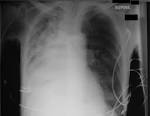

Atelectasis is defined as diminished volume affecting all or part of a lung. Note that the term atelectasis is typically used when there is partial. It may include a lung subsegment or the entire lung and is almost always a secondary. Collapsed Lung (Atelectasis) - Cedars-Sinai Learn more about collapsed lung (atelectasis including symptoms, prevention, causes and risk factors, diagnosis and treatment). Atelectasis - , the free encyclopedia Atelectasis is the collapse or closure of a lung resulting in reduced or absent gas exchange.

It may affect part or all of a lung. Org Lung atelectasis refers to collapse or incomplete expansion of pulmonary parenchyma. Atelectasis (at-uh-LEK-tuh-sis) is a condition in which one or more areas of your lungs collapse or don t inflate properly.

Atelectasis refers to collapse of part of the lung. Atelectasis - Mayo Clinic Atelectasis (at-uh-LEK-tuh-sis) a complete or partial collapse of a lung or lobe of a lung develops when the tiny air sacs (alveoli) within the lung become.

If only a small area or a. Atelectasis can occur if the lungs can t fully expand and fill with air. Atelectasis Causes - Mayo Clinic Atelectasis Comprehensive overview covers symptoms and causes of a partly or completely collapsed lung. Learn about Atelectasis symptoms, diagnosis and treatment in the Merck Manual. Atelectasis Treatment Management: Medical Care, Surgical Care The term atelectasis is derived from the Greek words ateles and ektasis, which mean. NHLBI, NIH - National Heart, Lung, and.